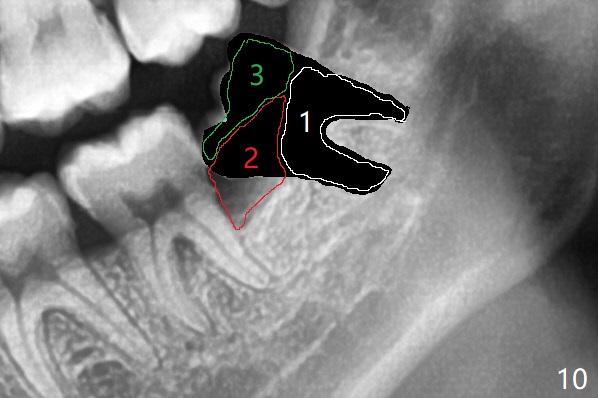

When the tooth #17 is extracted (Fig.9; 23 years old), collagen plug is inserted into the root portion of the sockets (Fig.10: 1 (white outline)), Vanilla graft is placed against the distal surface of #18 (2 (red outline)) and Osteogen plug (3 (green outline)) is placed coronally (3 steps). There is no bony defect associated with the distal surface of the tooth #18 immediate postop (Fig.11 (red dashed line: bone graft)). The wound heals in 2 weeks.